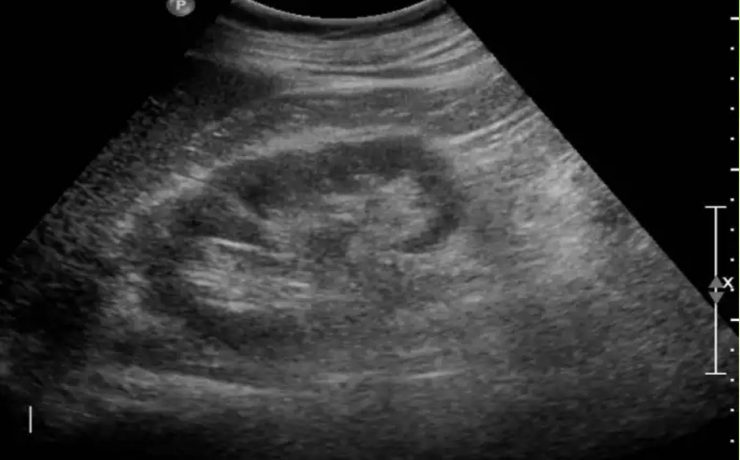

En este estudio se analiza la utilidad del ultrasonido en el estudio de la paciente estéril, específicamente con ultrasonido con aplicación de doppler, de Power doppler y la ecografía 3D para analizar los cambios cualitativos y cuantitativos que se observan en la irrigación del ovario en pacientes estériles, en pacientes